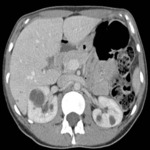

Tomografia computadorizada (TC) do abdome e da pelve de um paciente com doença leve

Da coleção do Dr. M. Hogan